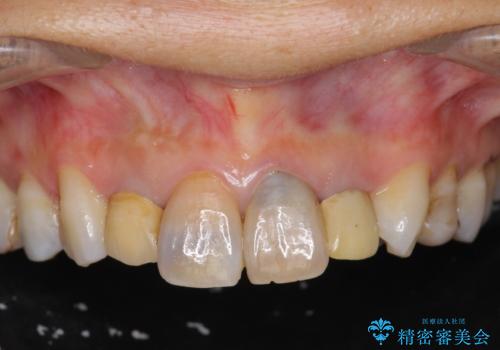

黒ずんだ見栄えの悪い前歯をきれいにしたい

- 「黒ずんで、見栄えの悪い前歯をきれいにしたい。」と、前歯のセラミック治療を希望され来院されました。

全て根管治療のすでになされている歯の変色で、オールセラミッククラウンによる審美性の改善を計画します。